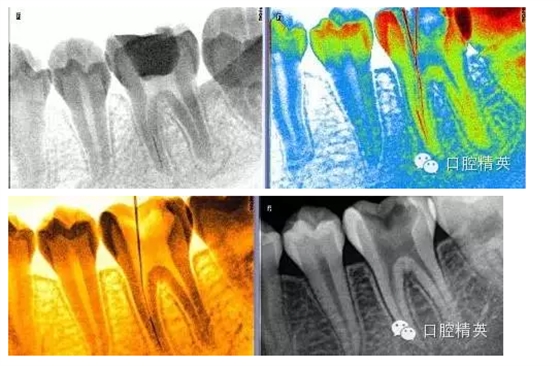

3,術(shù)前左下6近中根管斷針X-P,斷針長度約4MM,根尖慢性炎癥影像。。。

9,斷針取出術(shù)后X-P,RCT待續(xù)。。。